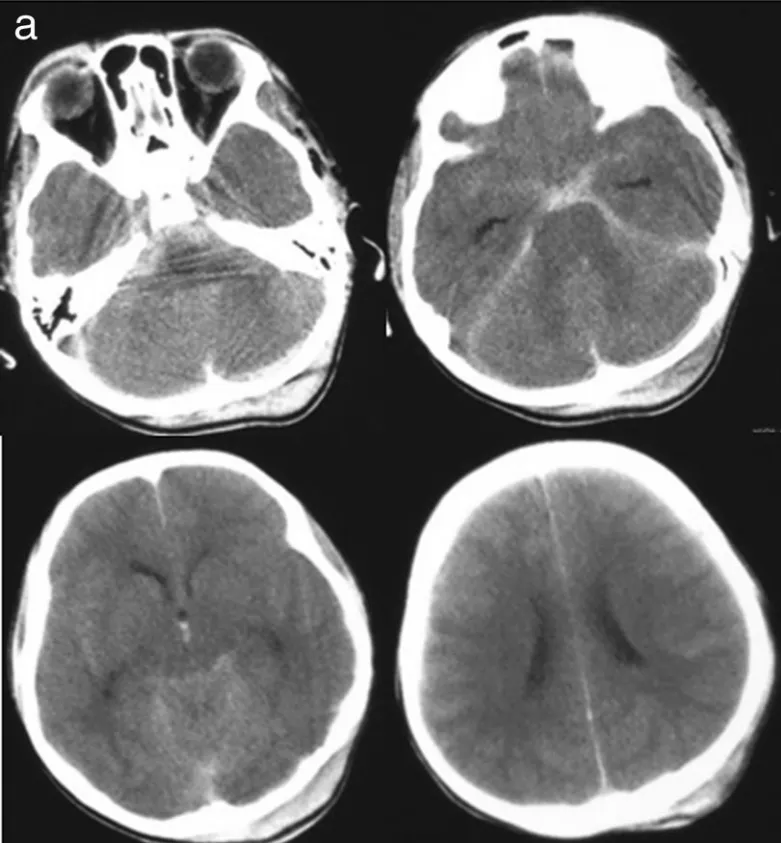

尽管大多数颅内血管畸形被认为是在先天基础上形成的,但它们在产前极少被发现,在新生儿和婴儿中也并不常见。这一特定患者群体的临床表现,最常见的特点是由大体积颅内出血引起的颅内...